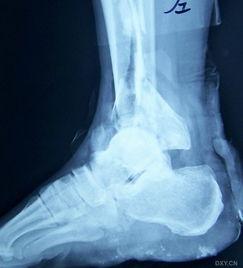

视频接着展示了医生对男子进行诊断的过程。医生首先询问了男子的受伤经过,然后仔细观察了他的小腿。在确认了骨折的位置后,医生用X光片进一步确认了骨折的程度。这一环节让我们看到了医生的专业素养和严谨的工作态度。